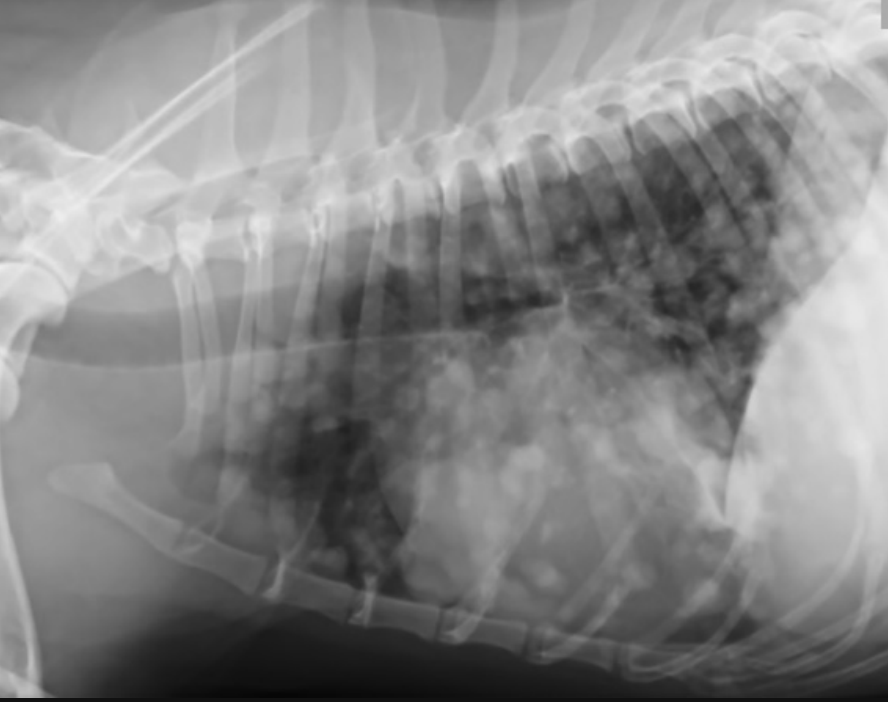

-thoracic imaging (radiographs or CT)

what is the purpose of thoracic imaging when diagnosing hemangiosarcoma?

search for mets:

-described as nodular to interstitial coalescing miliary pattern (ill-defined, fuzzy appearance)

radiographs: 78% sensitivity for detecting mets (false negative rate decreases w/ 3 views)